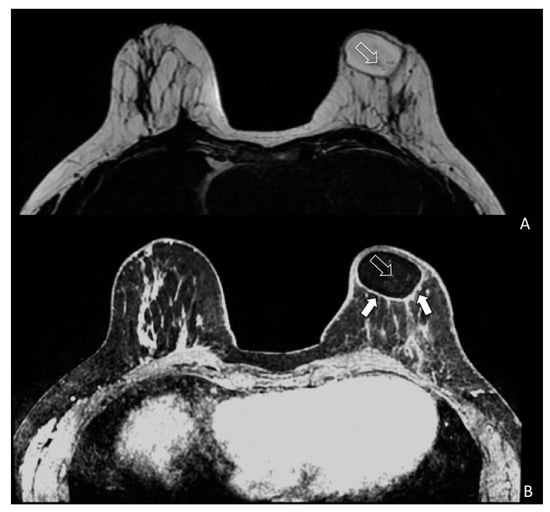

During breast surveillance, any tissue modification needs to be well known to avoid misleading interpretation between benign and malignant growth. To better identify the glandular and adipose tissues, a multimodal imaging approach seems to give the right answer for studying breast tissue modification following fat grafting. Figure 4 showed the physiological modifications of the breast tissue and evaluate fat replication throughout neo-angiogenesis. In particular, Figure 4 demonstrates how the vascularity of the left breast is increased when compared to the contralateral breast after fat grafting.

Figure 4. Bilateral three-dimensional MRI T1-weighted spoiled turbo gradient echo image after contrast media administration (colored superimposed image). Using a special fat saturation and separate shim volumes on each breast, VIBRANT sequence (Volume Imaging for Breast Assessment) allows axial acquisition with an excellent separation of glandular tissue (white arrows) from fat tissue (white empty arrows). The velvet region of interest shows how the vascularity of the left breast compared to the contralateral breast after fat grafting is increased.

Cyst formation, micro, macro—calcifications and cytosteatonecrotic areas (Figure 5A,B) were detected by MRI. Fat necrosis was present in four patients in the study group and in one of patients in the control group (p = 0.103). Fat necrosis was surgically removed and the pathological findings confirmed this diagnosis for three patients. One patient was observed and the ultrasound follow-up showed no need for intervention. In the long-term follow-up, adverse events, like infections and skin necrosis, were not observed in both groups.

Figure 5. Magnetic resonance imaging (MRI) of a patient (SG) treated with EF-e-A. (A) Axial MRI T2-weighted turbo spin echo image of both breasts. Fat is imaged with hyper-intense signal and glandular tissue with the matrix is characterized by hypo-intense signal. In the left breast is showed an oval area of hyper-intense signal representing the fat grafting. Very small vessels are depicted in the area (white empty arrow); (B) Bilateral three-dimensional T1-weighted spoiled turbo gradient echo image after contrast media administration VIBRANT sequence showed contrast uptake of the glandular tissue and of the fat graft boundary (white arrows). In this sequence, fat graft is characterized by hypo-intense signal due to the fat saturation pulse. In the fat graft, small vessels characterized by contrast media uptake are confirmed (white empty arrow).